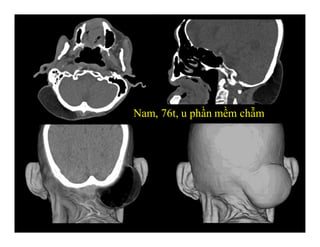

Nam, 76t, u phần mềm chẫm

Nam, 76t, uphần mềm chẫm